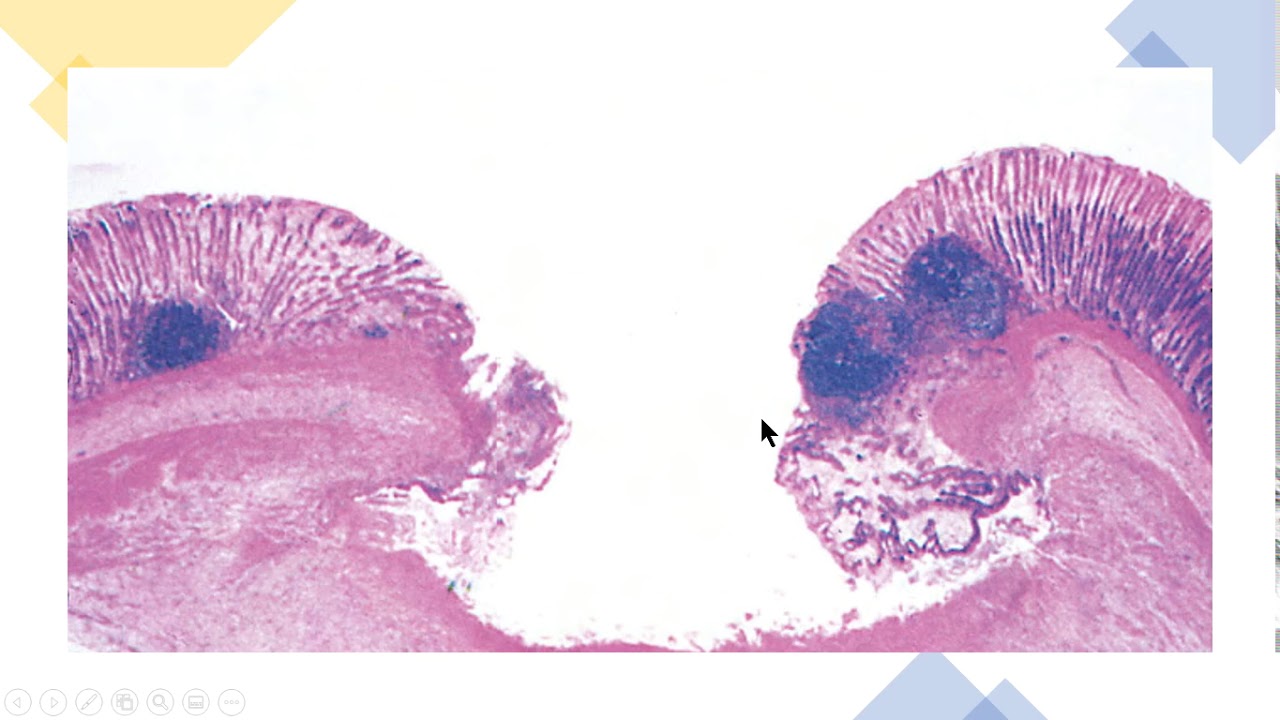

corte histológico um corte transversal da pele a gente vê aqueles camadas da pele né então você vê a epiderme a derme bom então você vê que são que é um tecido aqui tem uma a fibra queratina então a tecido epitelial estratificado queratinizado ar tão aqui ó essas essas camadinhas de célula que a gente chama de epiderme certo disso aqui a epiderme tá tudo e dar aqui para baixo é tecido conjuntivo tecido conjuntivo com fibroblastos esses núcleos a questão fibroblastos são células que produzem colágeno então a gente tem tecido conjuntivo que sustentando o tecido epitelial e

aqui a gente vê que é um corte de uma bolha pela bolha de água lei que formando uma queimadura então a gente vê aqui que logo abaixo da epiderme ficou esses passos branquiçado aqui e nada mais é do que uma efusão que é o que é uma coleção de líquido no caso aqui de água formando uma bolha o corte histológico de uma bolha bom então a gente vê que no processo inflamatório agudo as alterações vasculares o som característico por fluxo sanguíneo aumentado devido à dilatação das arteríolas e do leite capilar então você tem eritema vermelhidão